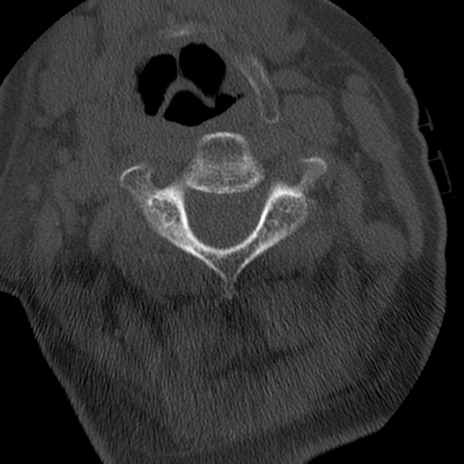

症例50 頚椎CT(横断像)

異常所見と診断は?

頚椎CT

矢状断像